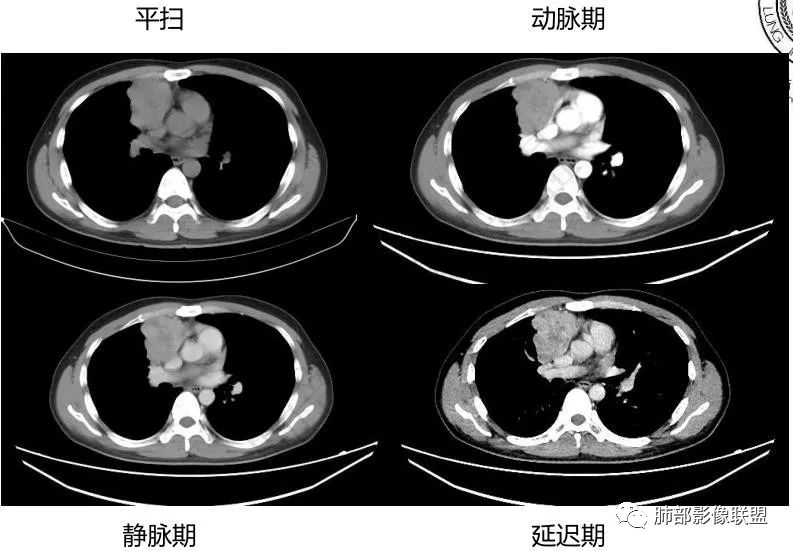

4、绒毛膜癌

纵隔原发性绒毛癌病人几乎为男性,也是高度恶性生殖细胞肿瘤,血、尿β-HCG升高是绒毛膜癌的一个特征,男性乳房发育,影像表现呈分叶状巨大肿块,亦出血坏死,富血供病变,易侵犯血管,所以早期容易出血转移,最常累及的器官为肺。

男性,12岁,绒癌伴双肺转移